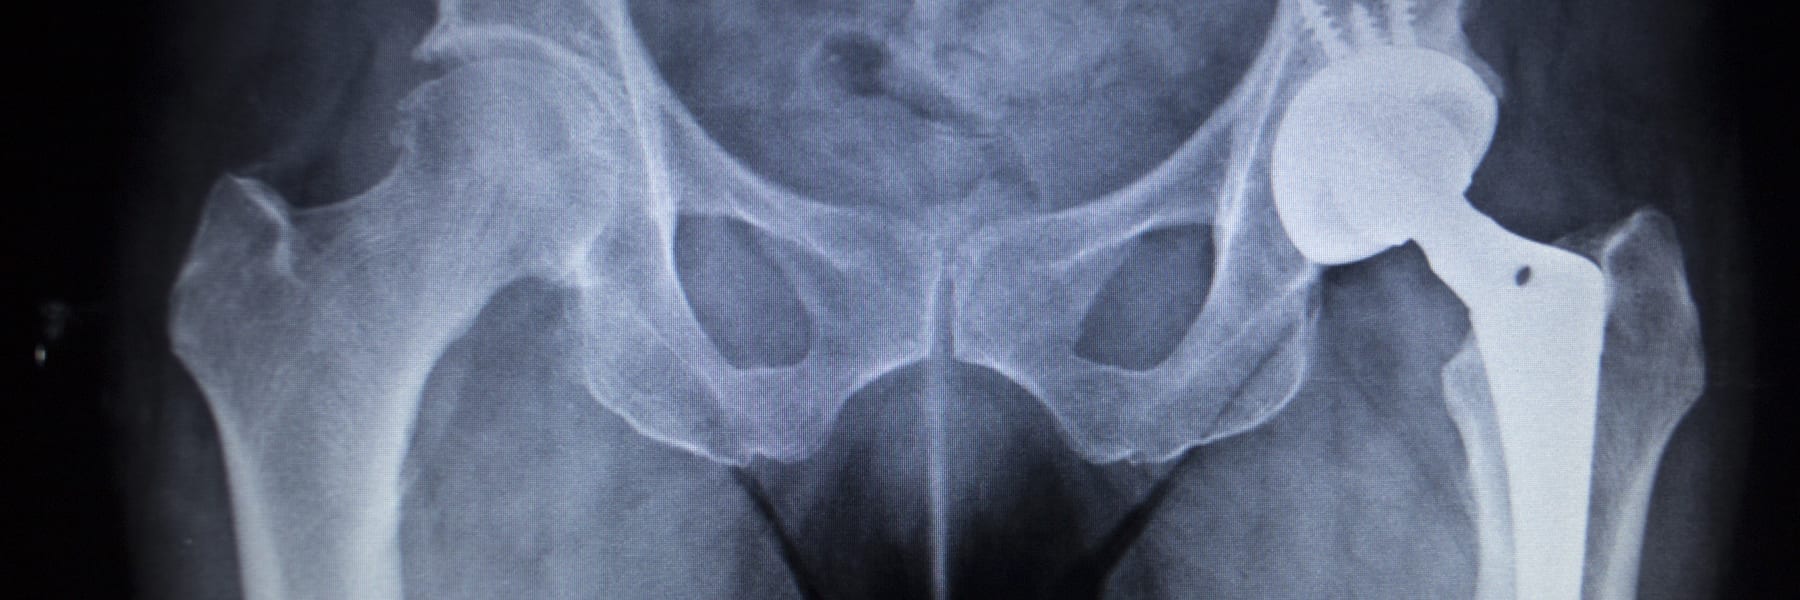

Fracture After Total Hip Replacement OrthoInfo AAOS Hip Replacement Recall Metal Toxicity A painful mom hip arthroplasty has various intrinsic and extrinsic causes (table 1). Hundreds of thousands of patients around the world may have been exposed to toxic substances after being implanted with poorly regulated and potentially dangerous hip. As in all painful tha,5 a thorough clinical history, a. In mom hip implants, the. Metal‐on‐metal (mom) hip resurfacing has recently been. Hip Replacement Recall Metal Toxicity.

Fracture After Total Hip Replacement OrthoInfo AAOS Hip Replacement Recall Metal Toxicity A painful mom hip arthroplasty has various intrinsic and extrinsic causes (table 1). Hundreds of thousands of patients around the world may have been exposed to toxic substances after being implanted with poorly regulated and potentially dangerous hip. As in all painful tha,5 a thorough clinical history, a. Metal‐on‐metal (mom) hip resurfacing has recently been a popular prosthesis choice for. Hip Replacement Recall Metal Toxicity.

2023 Update on Exactech Hip, Knee, and Ankle Implant Recall Lawsuits Hip Replacement Recall Metal Toxicity A painful mom hip arthroplasty has various intrinsic and extrinsic causes (table 1). Cobalt was widely used for hip and knee joint replacements until cases of heavy metal poisoning appeared. In mom hip implants, the. Hundreds of thousands of patients around the world may have been exposed to toxic substances after being implanted with poorly regulated and potentially dangerous hip.. Hip Replacement Recall Metal Toxicity.